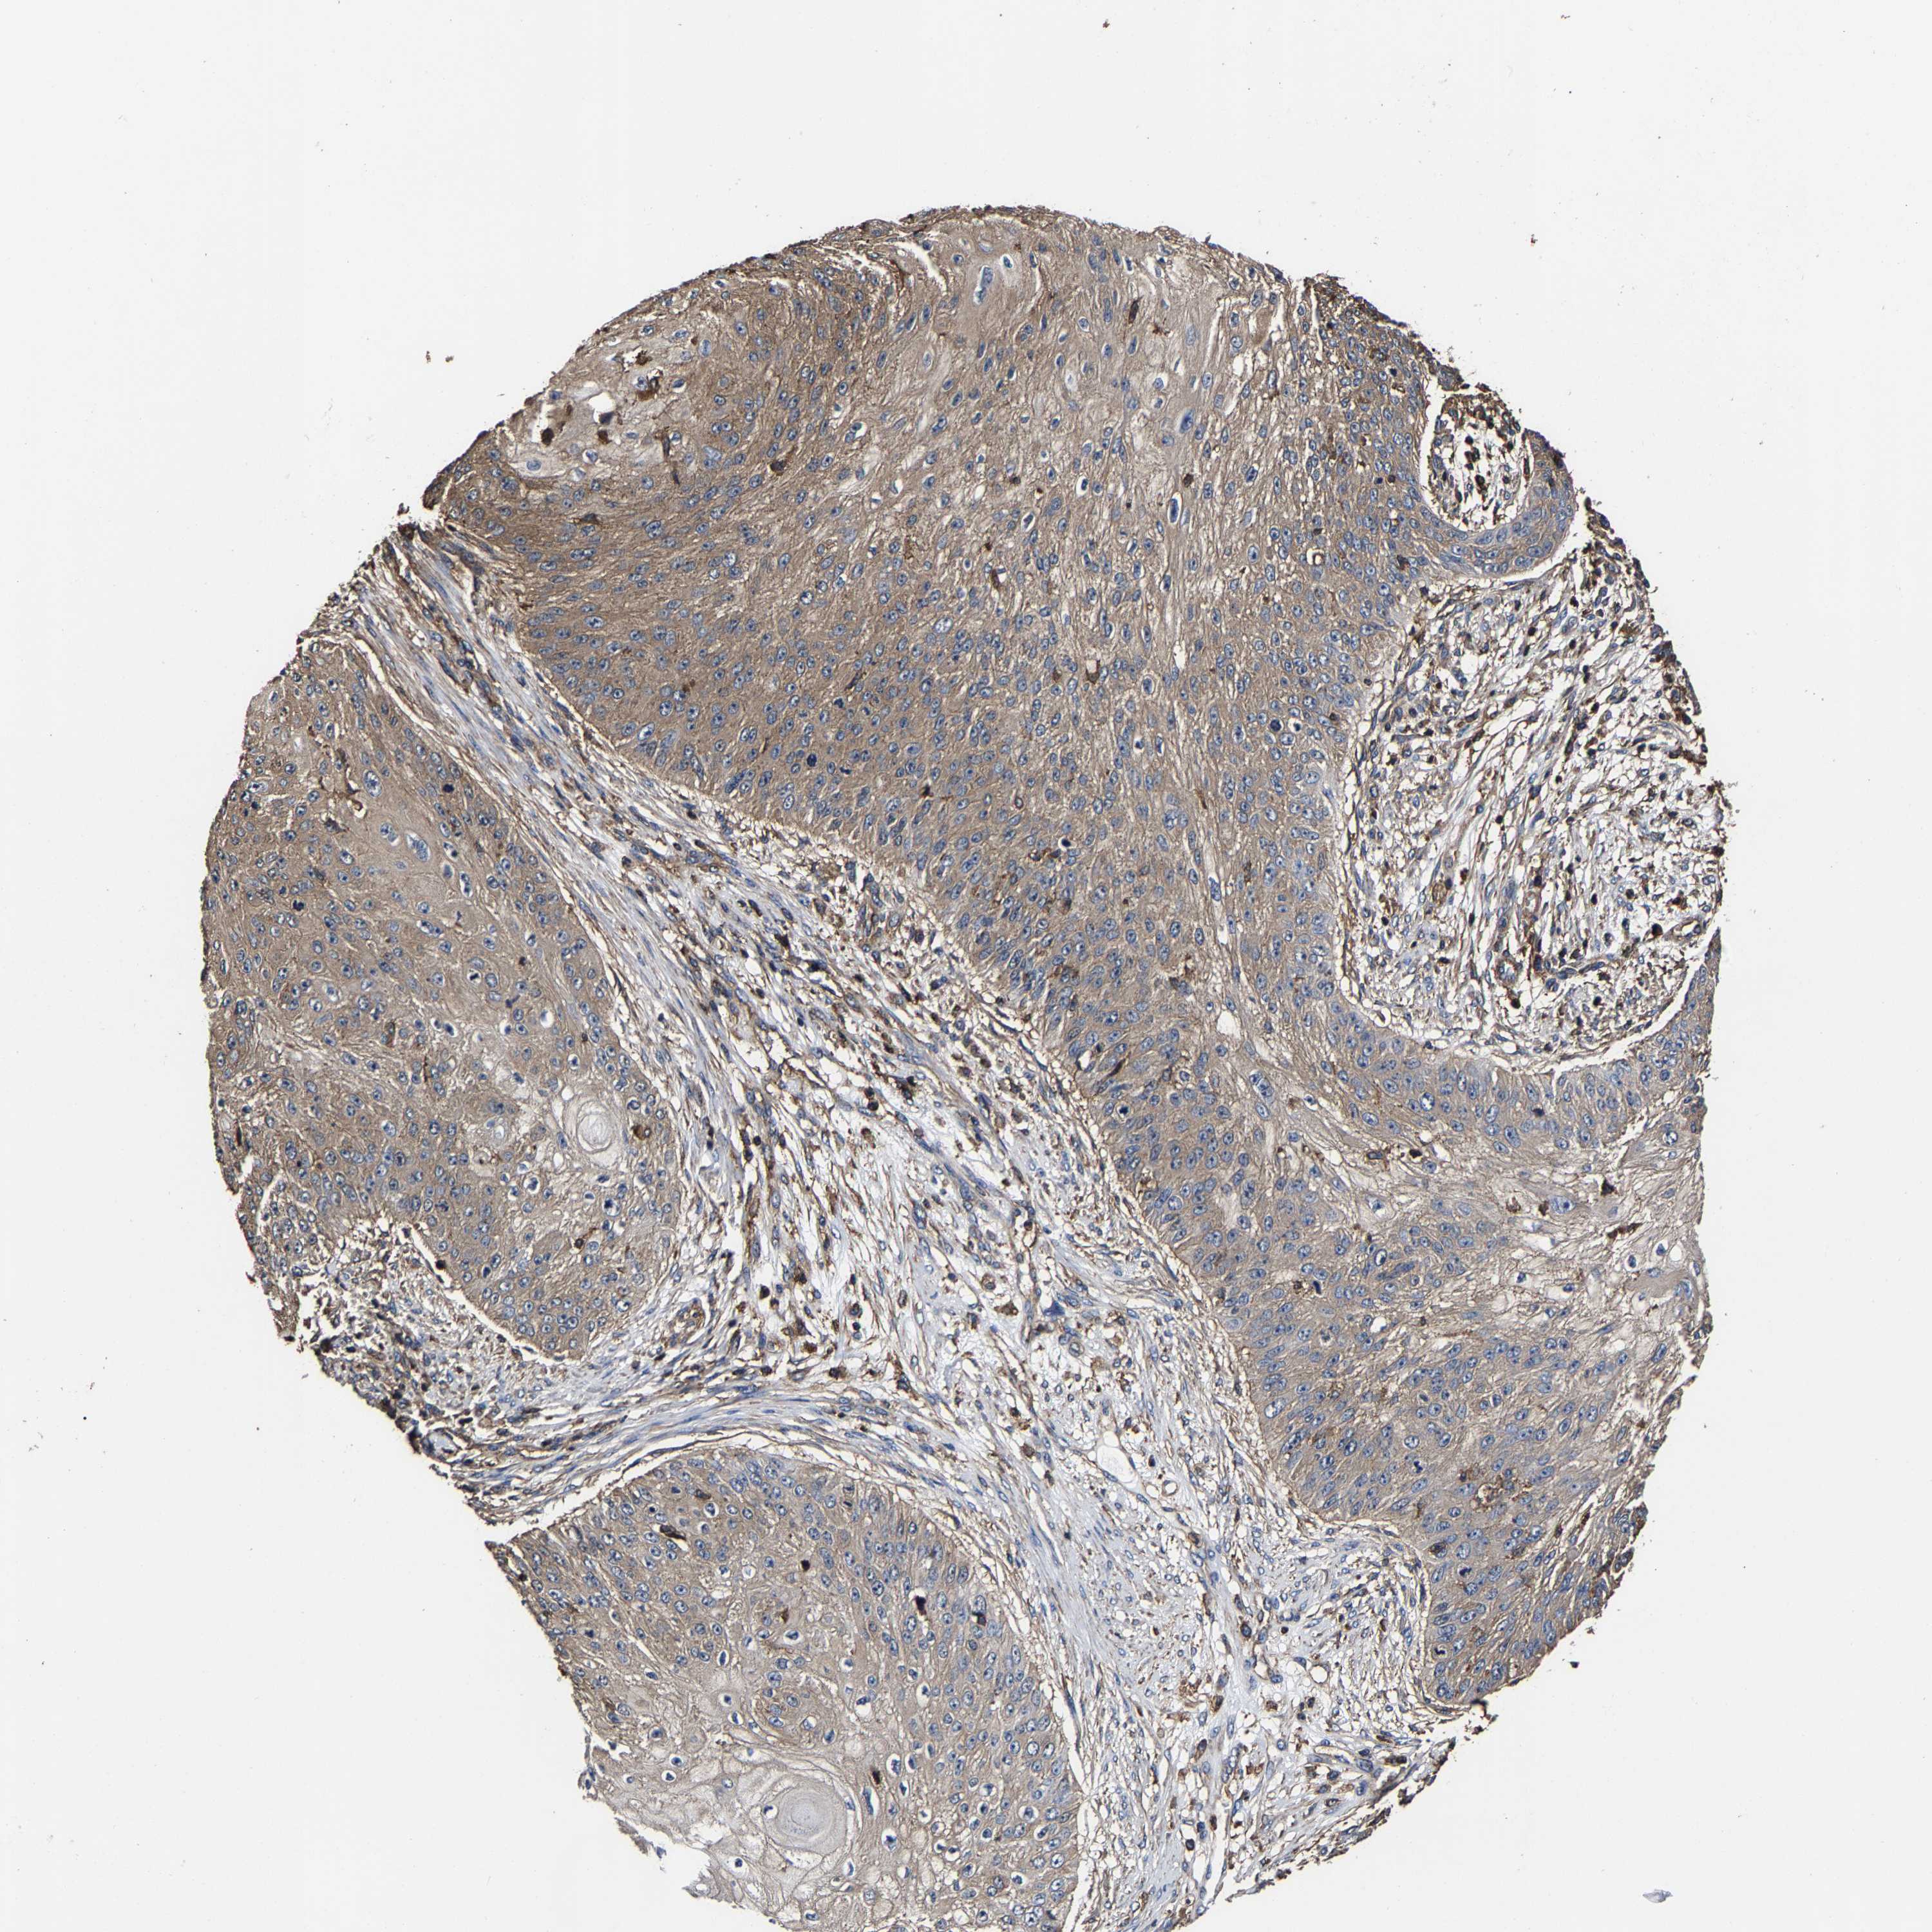

SKIN CANCER - Protein expressioni

A mouse-over function shows sample information and annotation data. Click on an image to view it in a full screen mode. Samples can be filtered based on level of antibody staining by selecting one or several of the following categories: high, medium, low and not detected. The assay and annotation is described here.

Antibody stainingi

Antibody staining in the annotated cell types in the current human tissue is reported as not detected, low, medium, or high, based on conventional immunohistochemistry profiling in selected tissues. This score is based on the combination of the staining intensity and fraction of stained cells.

Each image is clickable and will lead to virtual microscopy that enables deeper exploration of all samples and also displays staining intensity scores, fraction scores and subcellular localization as well as patient and tissue information for each sample.

Antibody HPA019949

Staining

High

Medium

Low

Not detected

Intensity

Strong

Moderate

Weak

Negative

Quantity

>75%

75%-25%

<25%

None

Location

Nuclear

Cytoplasmic/membranous

Cytoplasmic/membranous,nuclear

Squamous cell carcinoma in situ, NOS

Squamous cell carcinoma, NOS

Squamous cell carcinoma, metastatic, NOS

Basal cell carcinoma